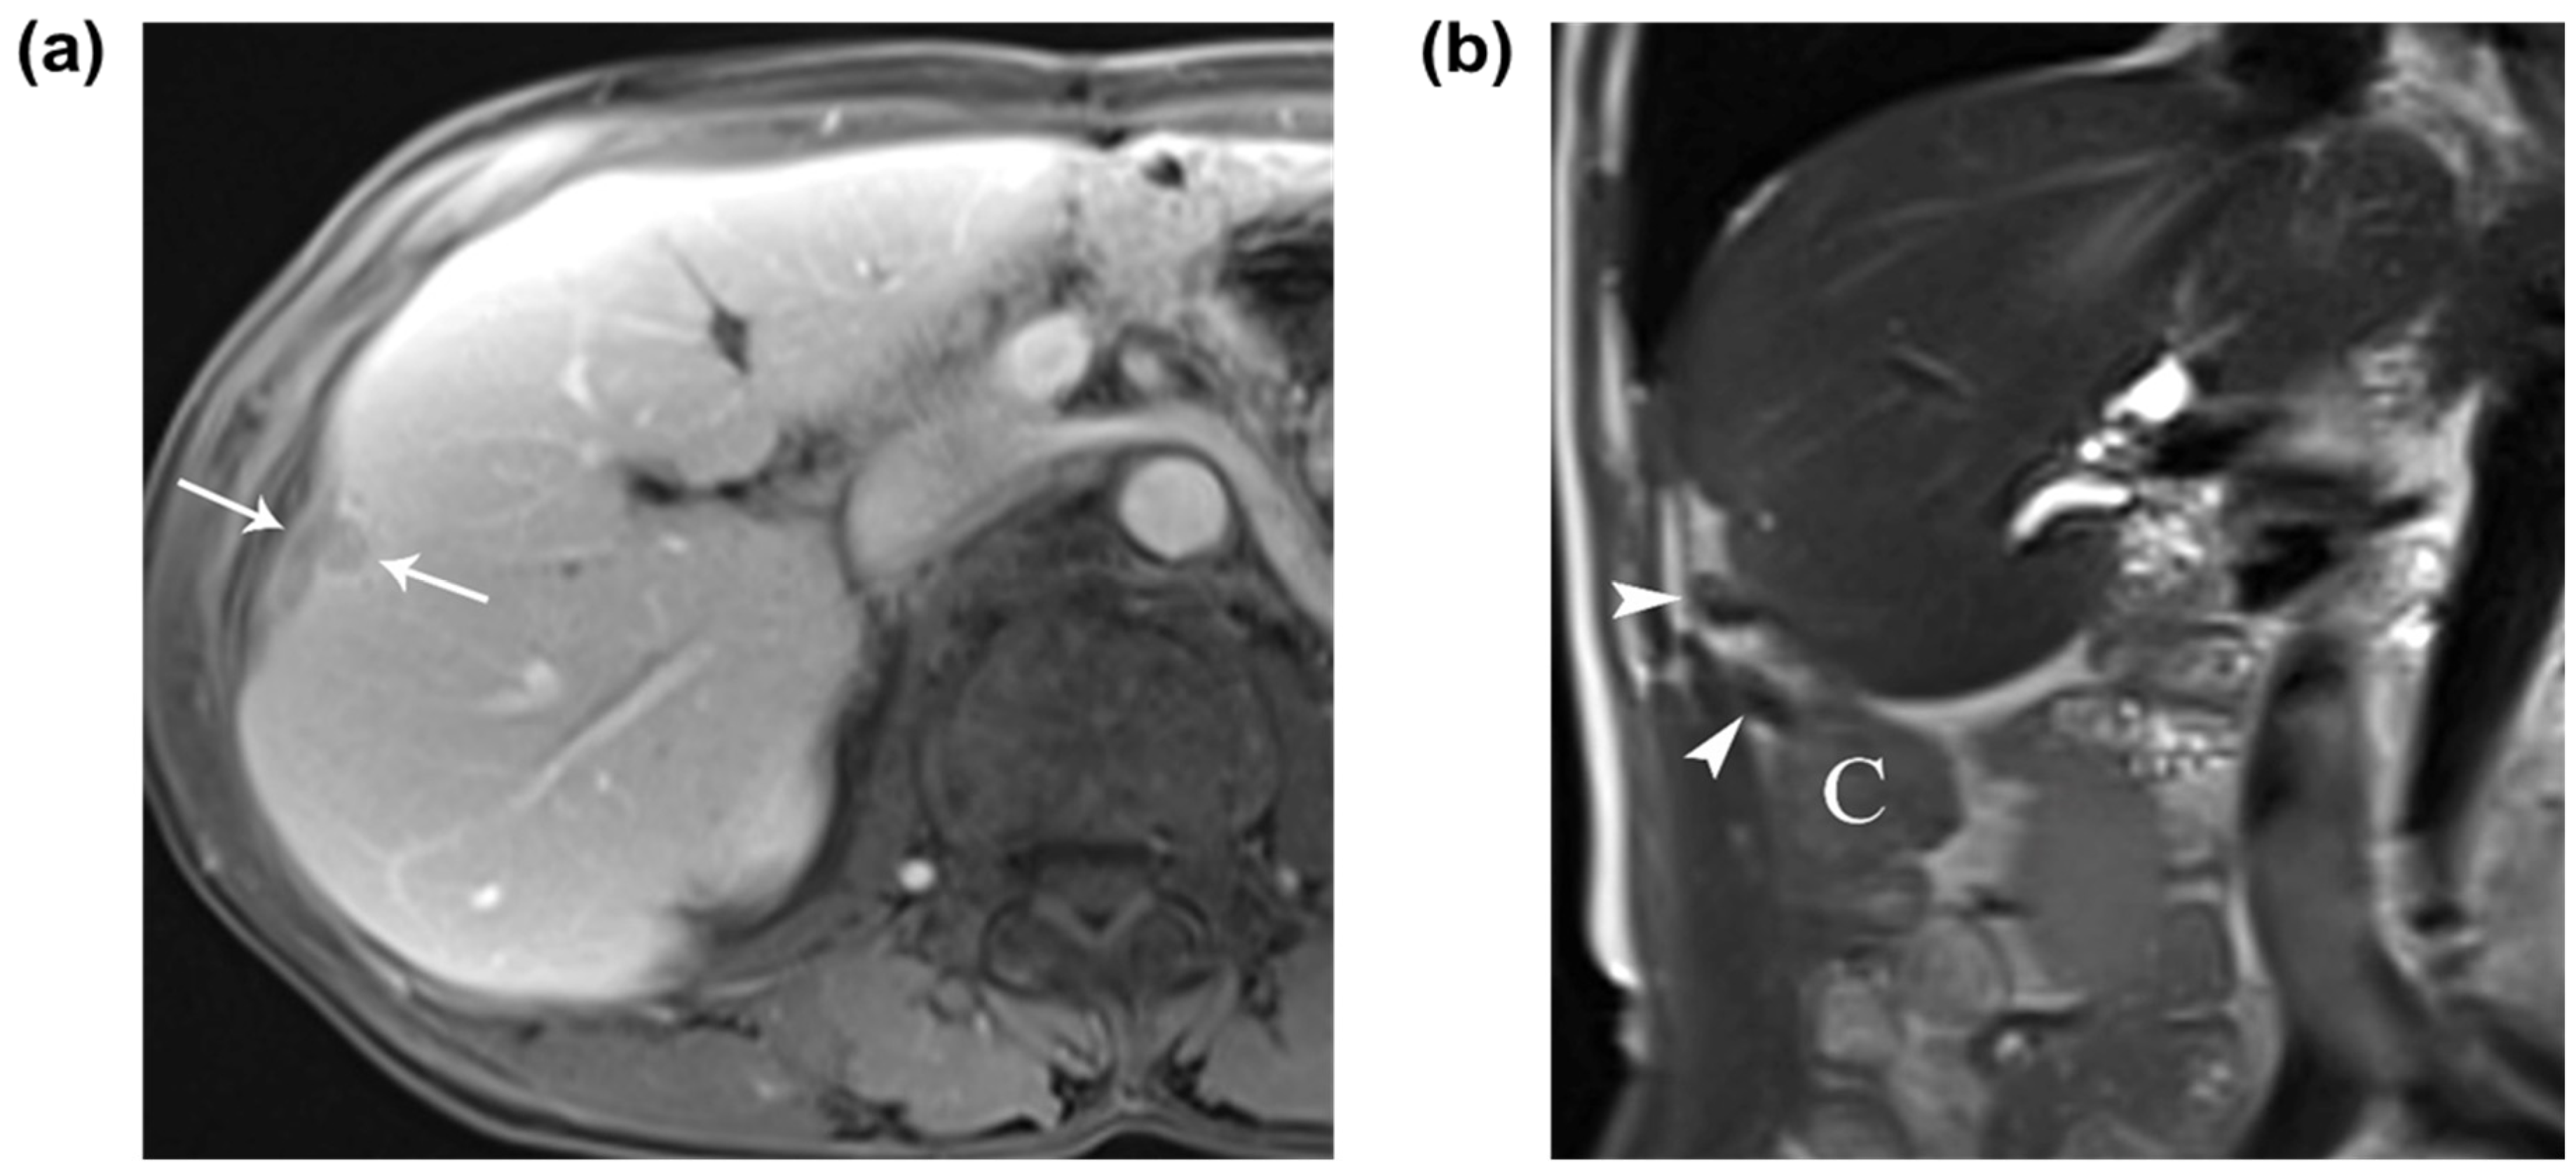

A 69-year-old man was admitted to our hospital for the evaluation and treatment of a hepatic mass. He had a history of pylorus-preserving pancreaticoduodenectomy and adjuvant chemotherapy for cholangiocarcinoma in the distal common bile duct 11 years previously and had developed liver cirrhosis due to alcohol abuse. Upon admission, laboratory findings were unremarkable. Contrast-enhanced computed tomography (CT) and gadoxetic-acid-enhanced magnetic resonance imaging (MRI) were performed to evaluate the hepatic mass. The MRI showed a 1.2 cm subcapsular hepatic nodule with typical findings of HCC in segment 5 of the liver, located adjacent to the cecum and ascending colon (Figure 1). Although the hepatic nodule has typical imaging findings of HCC, the possibility of hepatic metastasis cannot be ruled out. Thus, we decided to perform a percutaneous ultrasound (US)-guided core needle biopsy to distinguish between hepatic metastasis and HCC. RFA was selected as the treatment of choice after the nodule was confirmed to be HCC. RFA was performed under intravenous and local anesthesia. Before electrode placement, hydrodissection using 1 L of 5% dextrose solution was introduced under US guidance to minimize thermal injury to the adjacent colon. Tumor ablation was performed for 8 min after the placement of electrodes. A 1.2 cm subcapsular hepatocellular carcinoma in segment 5 of the liver in a 69-year-old man. (a) Contrast-enhanced axial T1-weighted MR image shows the washout of a 1.2 cm subcapsular hepatocellular carcinoma (arrows) on the portal venous phase. (b) A coronal T2-weighted MR image shows the perihepatic location of the appendix (arrowheads) and cecum (C) around the hepatocellular carcinoma.